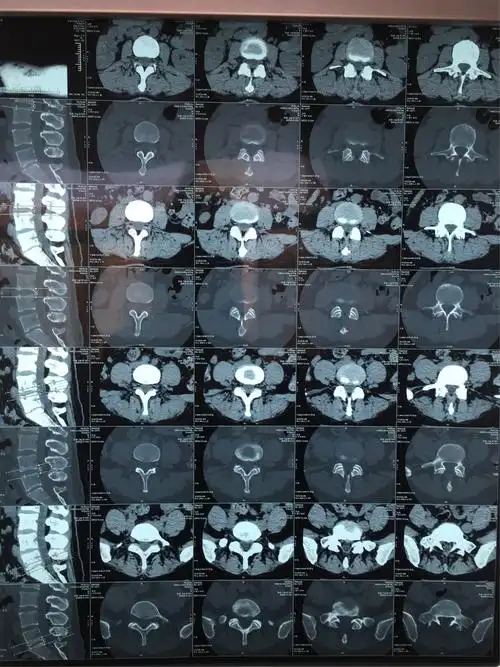

旁中央型腰间盘突出症病人.39岁女性病人